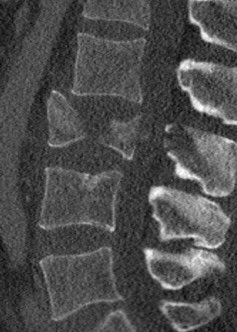

IM-0005-0083 L-spine.jpgIM-0003-0038 L3.jpgIM-0003-0031 L2.jpg

The fly-through doesn’t show the spinal injury very well, so here are some 2-D sections. The left panel is a section of my lumbar spine viewed from my left side; note the obviously smashed L3 vertebra. The middle panel is a top-view slide of L3, and the right panel is healthy L2 (the vertebra immediately above) for comparison.

1. Burst fracture of the L3 vertebra with “severe loss of ... height” and “central canal narrowing to 3mm” (yes that is where my spinal cord goes). Right transverse process (one of the bits that sticks out) of L3 also broken, but this was not displaced (i.e., the fragments not separated).